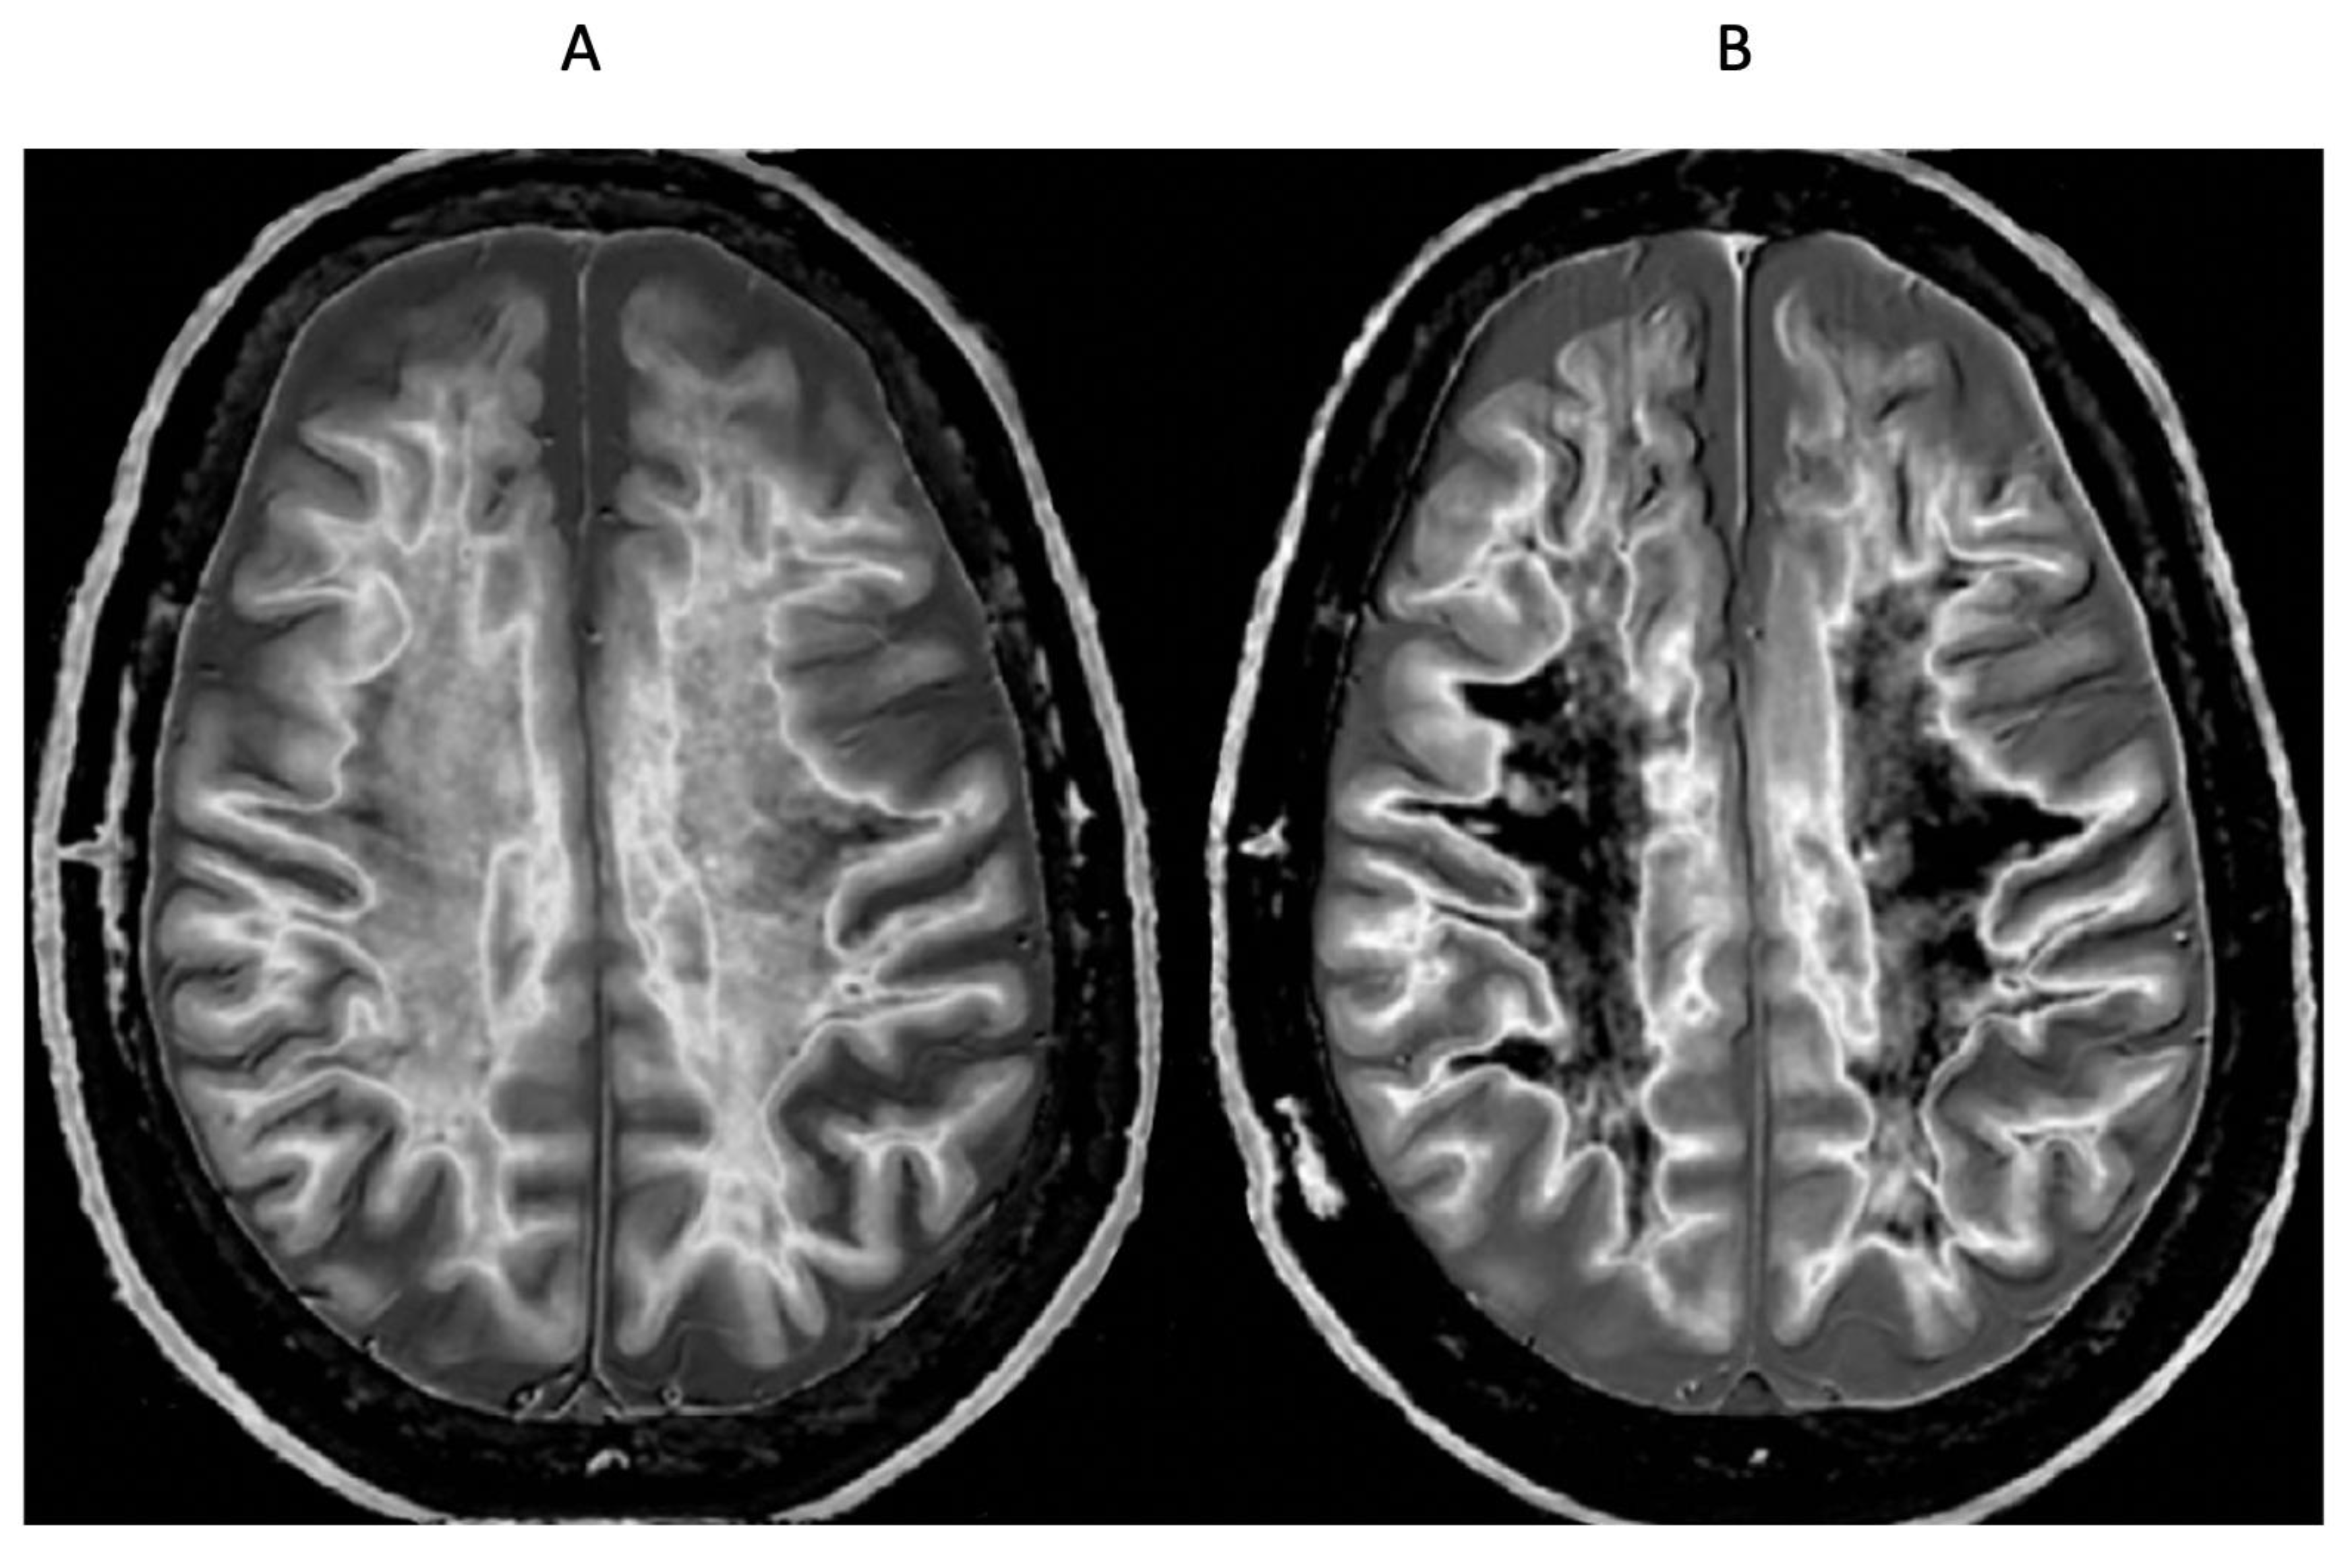

Figure 19.

51-year-old male patient with methamphetamine substance use disorder after one month’s abstinence (A) and after nine months’ abstinence (B). Positionally matched narrow mD dSIR (T1-BLAIR) images. In (A) there is extensive high signal in the white matter of the cerebral hemispheres with only small areas of normal or near normal white matter (dark) at the periphery of the white matter (whiteout sign, grade 4 out of 5). After nine months’ abstinence (B), the high signal areas in (A) have markedly regressed. There is some intermediate signal in the more central white matter and lower signal in the peripheral white matter (whiteout sign grade 2 out of 5, where grade 1 is normal). No abnormality was seen in either examination on the corresponding T2-FLAIR images. A previous mTBI in the patient may have been a confounder.